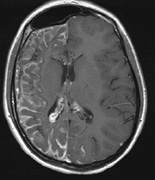

Fig. 5. Surveillance images from a 15-year-old boy with a history of visual loss, proptosis and a diagnosis of NF1. Postcontrast axial (a) and sagittal (b) T1-weighted images demonstrate a plexiform neurofibroma of the left upper and lower eyelids, which extends into the orbit and to the extraconal soft tissues through a widened superior orbital foramen, best seen in (c). An optic nerve glioma widens the optic canal. (d) A sphenoid wing dysplasia is visible and seen as asymmetry of the orbits on the 3D CT bone reconstruction images.

1. Perineural growth pattern, correlating with a diagnosis of NF1. The tumor expands in the subarachnoid space and the optic nerve is compressed as a central ribbon. On T2-weighted MRI, this may be seen as a low-intensity core with surrounding high-intensity rim. Increased tortuosity of the optic nerve is also associated with this growth pattern (Fig. 5).63